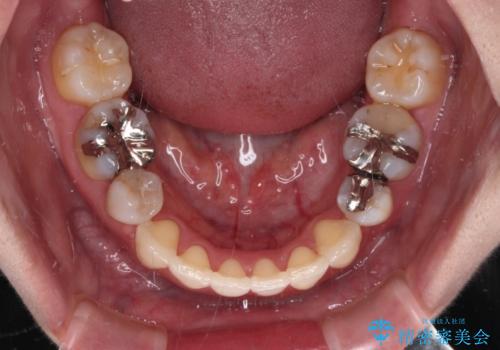

- 前歯のデコボコと上顎の前突感による口の閉じにくさを気にして来院された患者様です。

目立たない装置を希望されたので、上顎が裏側装置のハーフリンガルを選択し、上下左右の小臼歯(計4歯)を抜歯して矯正治療を行うこととしました。